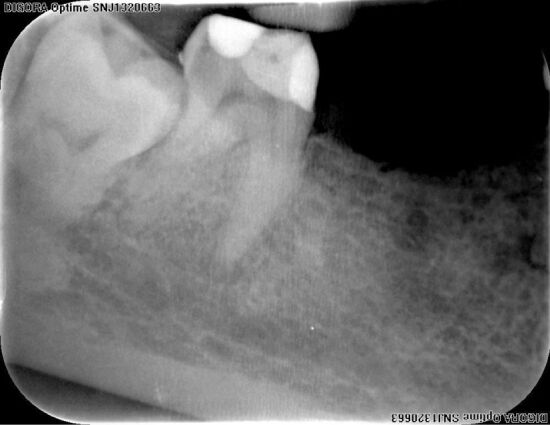

特别是在磨牙中,有时可能有异常的额外根管,个别病例中牙齿内部形态的复杂性有时与公认的分类规则不匹配,并突出了在牙髓治疗过程中错过解剖结构的风险。据我们所知,一个永久性下颌第二磨牙有五个独立的根,三个近中根和两个远端根,每个根都有一个根管,目前尚未报道。尽管治疗困难,但通过使用牙科手术显微镜和小视场的锥束计算机断层扫描(CBCT),可以成功地接近这颗牙齿。虽然CBCT不是一种常规的影像学检查,但在非典型牙齿解剖的情况下,旨在制定适当的诊断和治疗计划,成功的临床结果优于照射剂量。

Especially in molars that may have sometimes aberrant additional root canals, the complexity of tooth internal morphology in individual cases sometimes does not match to admitted classification rules and underlines the risk of missed anatomy during the endodontic management. To our knowledge, a permanent mandibular second molar with independent five roots, three mesial and two distal, each of them harboring a single canal, was not yet reported. Despite the treatment difficulties this tooth could be successfully approached by using dental operative microscope and cone-beam computed tomography (CBCT) with small field of view. Though CBCT is not a routine imagistic examination, in case of atypical tooth anatomy aiming to establish adequate diagnosis and treatment plan, the successful clinical outcome prevails over the irradiation dose.